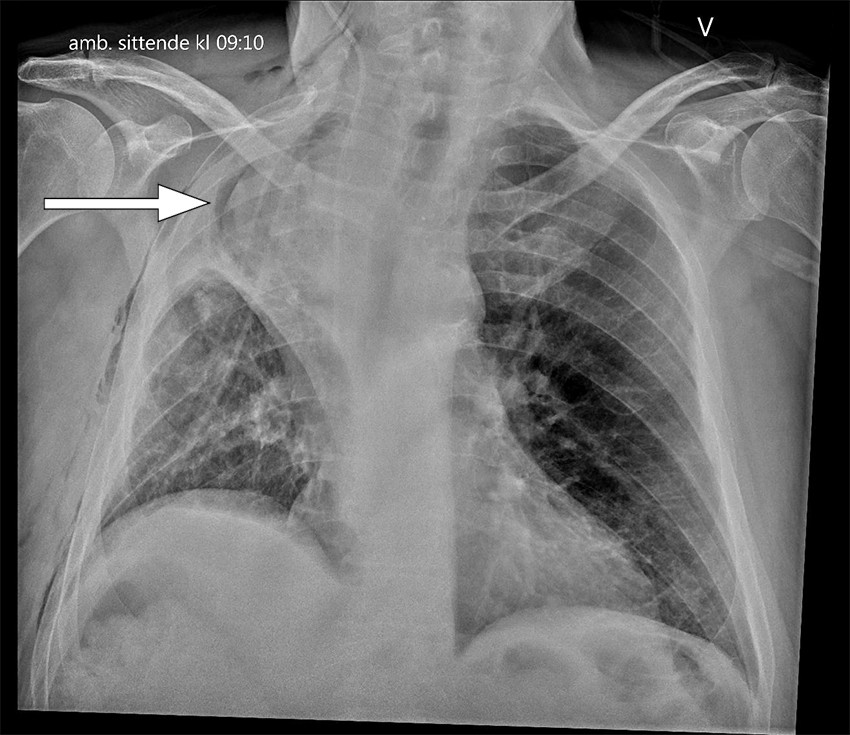

Rutinemessig postoperativ røntgen toraks viste atelektasepregede fortetninger i høyre lunges midtlapp. Det forelå også en liten høyresidig pneumotoraks og små mengder pleuravæske på samme side, som man kunne forvente etter operasjonen. Kontroll med røntgen toraks første postoperative dag viste økte fortetninger i øvre halvdel av høyre hemitoraks, som kunne være uttrykk for forverret atelektase, pleuravæske eller hemotoraks (figur 1). Pasienten var respiratorisk ubesværet og hadde god kapillær oksygenmetning på 96–98 % med oksygentilskudd 2 L/min på nesekateter. Det forelå ingen kliniske infeksjonstegn.